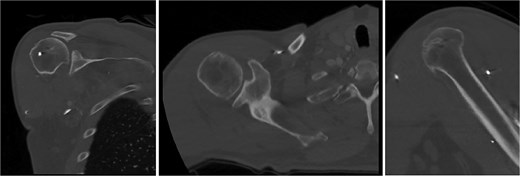

Both shoulders were reduced urgently by the orthopedic team, with immediate improvement in paresthesias (Fig. 2). Post-reduction CTs were significant for bilateral chronic rotator cuff disease with superior migration of the humeral heads, right-sided supraspinatus and subscapularis atrophy, and a left nondisplaced glenoid fracture (Figs 3 and 4). He was discharged home in bilateral slings.

Post-reduction CT of the left shoulder demonstrating superior humeral head migration relative to the glenoid.

Post-reduction CT of the right shoulder demonstrating superior humeral head migration relative to the glenoid, visualized evidence of prior rotator cuff repair surgery, and a nondisplaced anterior-inferior glenoid fracture.